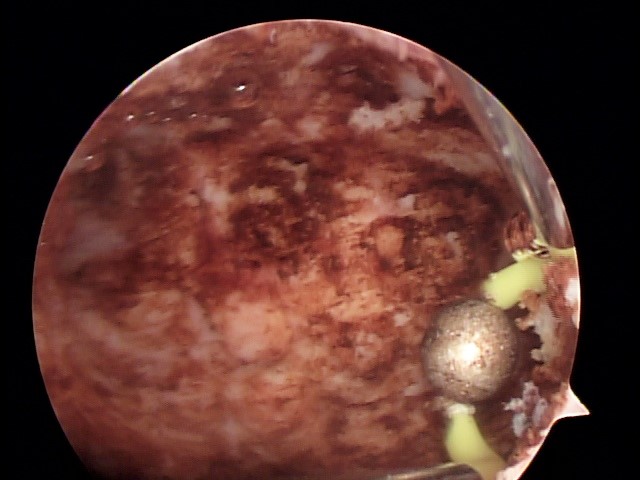

Os miomas uterinos são tumores que se desenvolvem de células da musculatura uterina, podendo crescer em direção ao interior no útero (Miomas submucosos). Eles estão diretamente relacionados a hemorragias, anemia e infertilidade.

Em geral, através da histeroscopia cirúrgica, miomas de até 05 centímetros podem ser retirados por completo, com todos os benefícios de um procedimento minimamente invasivo: sem cortes, em um único tempo cirúrgico e com rápida recuperação. Contudo, algumas pacientes podem ter particularidades antes e durante das cirurgias e mais de um tempo cirúrgico pode ser necessário.